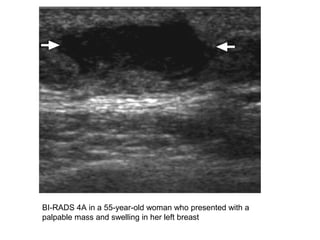

BI-RADS 4A in a 55-year-old woman who presented with a

palpable mass and swelling in her left breast

BI-RADS 4A ina 55-year-old woman who presented with a palpable mass and swelling in her left breast